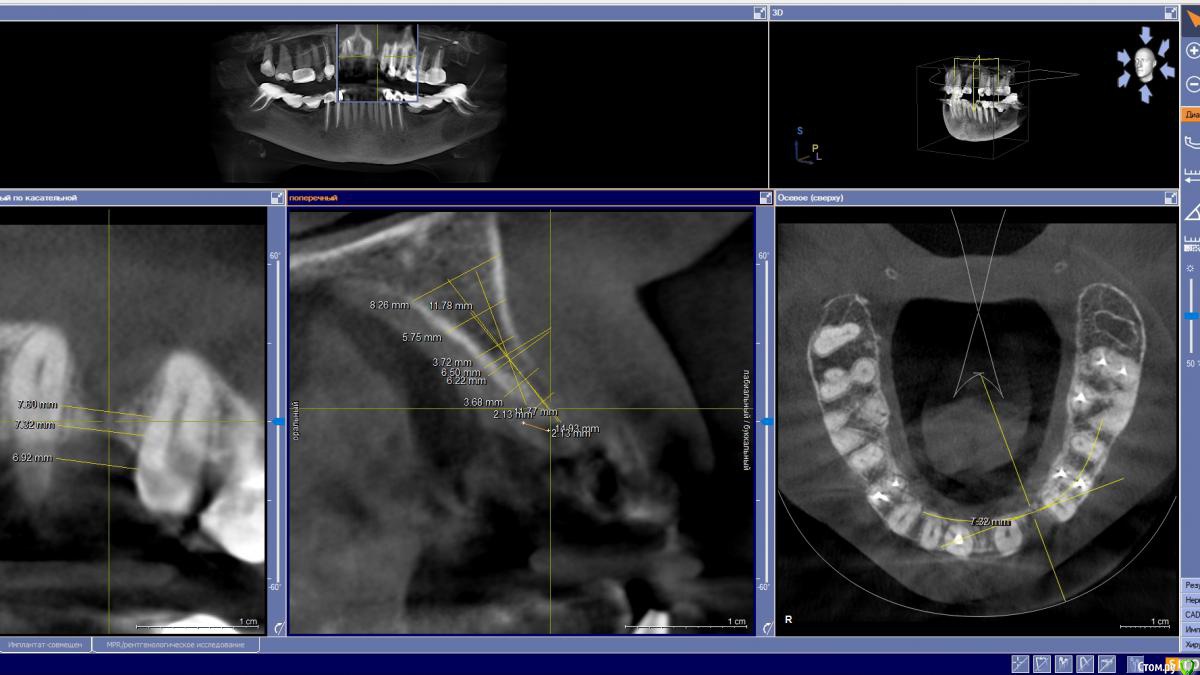

zumanok Опубликовано 22 марта, 2019 Поделиться Опубликовано 22 марта, 2019 (изменено) Господа, раз уж пошла такая пьянка. Посоветуйте с тактикой лечения. Буду весьма благодарен. Изменено 22 марта, 2019 пользователем zumanok Ссылка на комментарий

kramer Опубликовано 22 марта, 2019 Поделиться Опубликовано 22 марта, 2019 Господа, раз уж пошла такая пьянка. Посоветуйте с тактикой лечения. Буду весьма благодарен.Имплантат под заглушку + нкр с ПТФЕ мембраной, через 5 месяцев убрать мембрану и добавить толстый ССТ, через 6 недель поставить формирователь без больших разрезов, через 2 недели временную коронку. Я бы так делал. Медленно, зато прогнозируемо. Ссылка на комментарий

zumanok Опубликовано 22 марта, 2019 Поделиться Опубликовано 22 марта, 2019 Большое спасибо. Примерно так и планировал но без имлантации. Имплантат под заглушку + нкр с ПТФЕ мембраной, через 5 месяцев убрать мембрану и добавить толстый ССТ, через 6 недель поставить формирователь без больших разрезов, через 2 недели временную коронку. Я бы так делал. Медленно, зато прогнозируемо. 1 Ссылка на комментарий